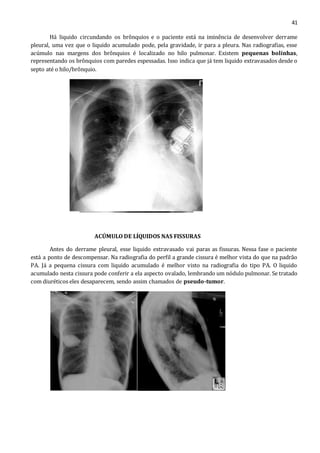

Há liquido circundando os brônquios e o paciente está na iminência de desenvolver derrame

pleural, uma vez que o liquido acumulado pode, pela gravidade, ir para a pleura. Nas radiografias, esse

acúmulo nas margens dos brônquios é localizado no hilo pulmonar. Existem pequenas bolinhas,

representando os brônquios com paredes espessadas. Isso indica que já tem liquido extravasados desde o

septo até o hilo/brônquio.